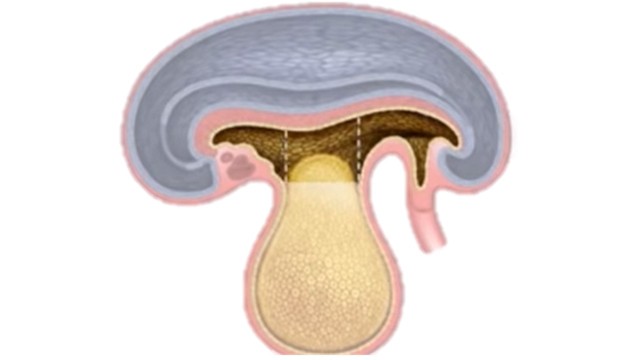

• Hernia del cordón umbilical

Hernia del cordón umbilical

SEMANA 6

• Regresa la hernia fisiológica

SEMANA 12